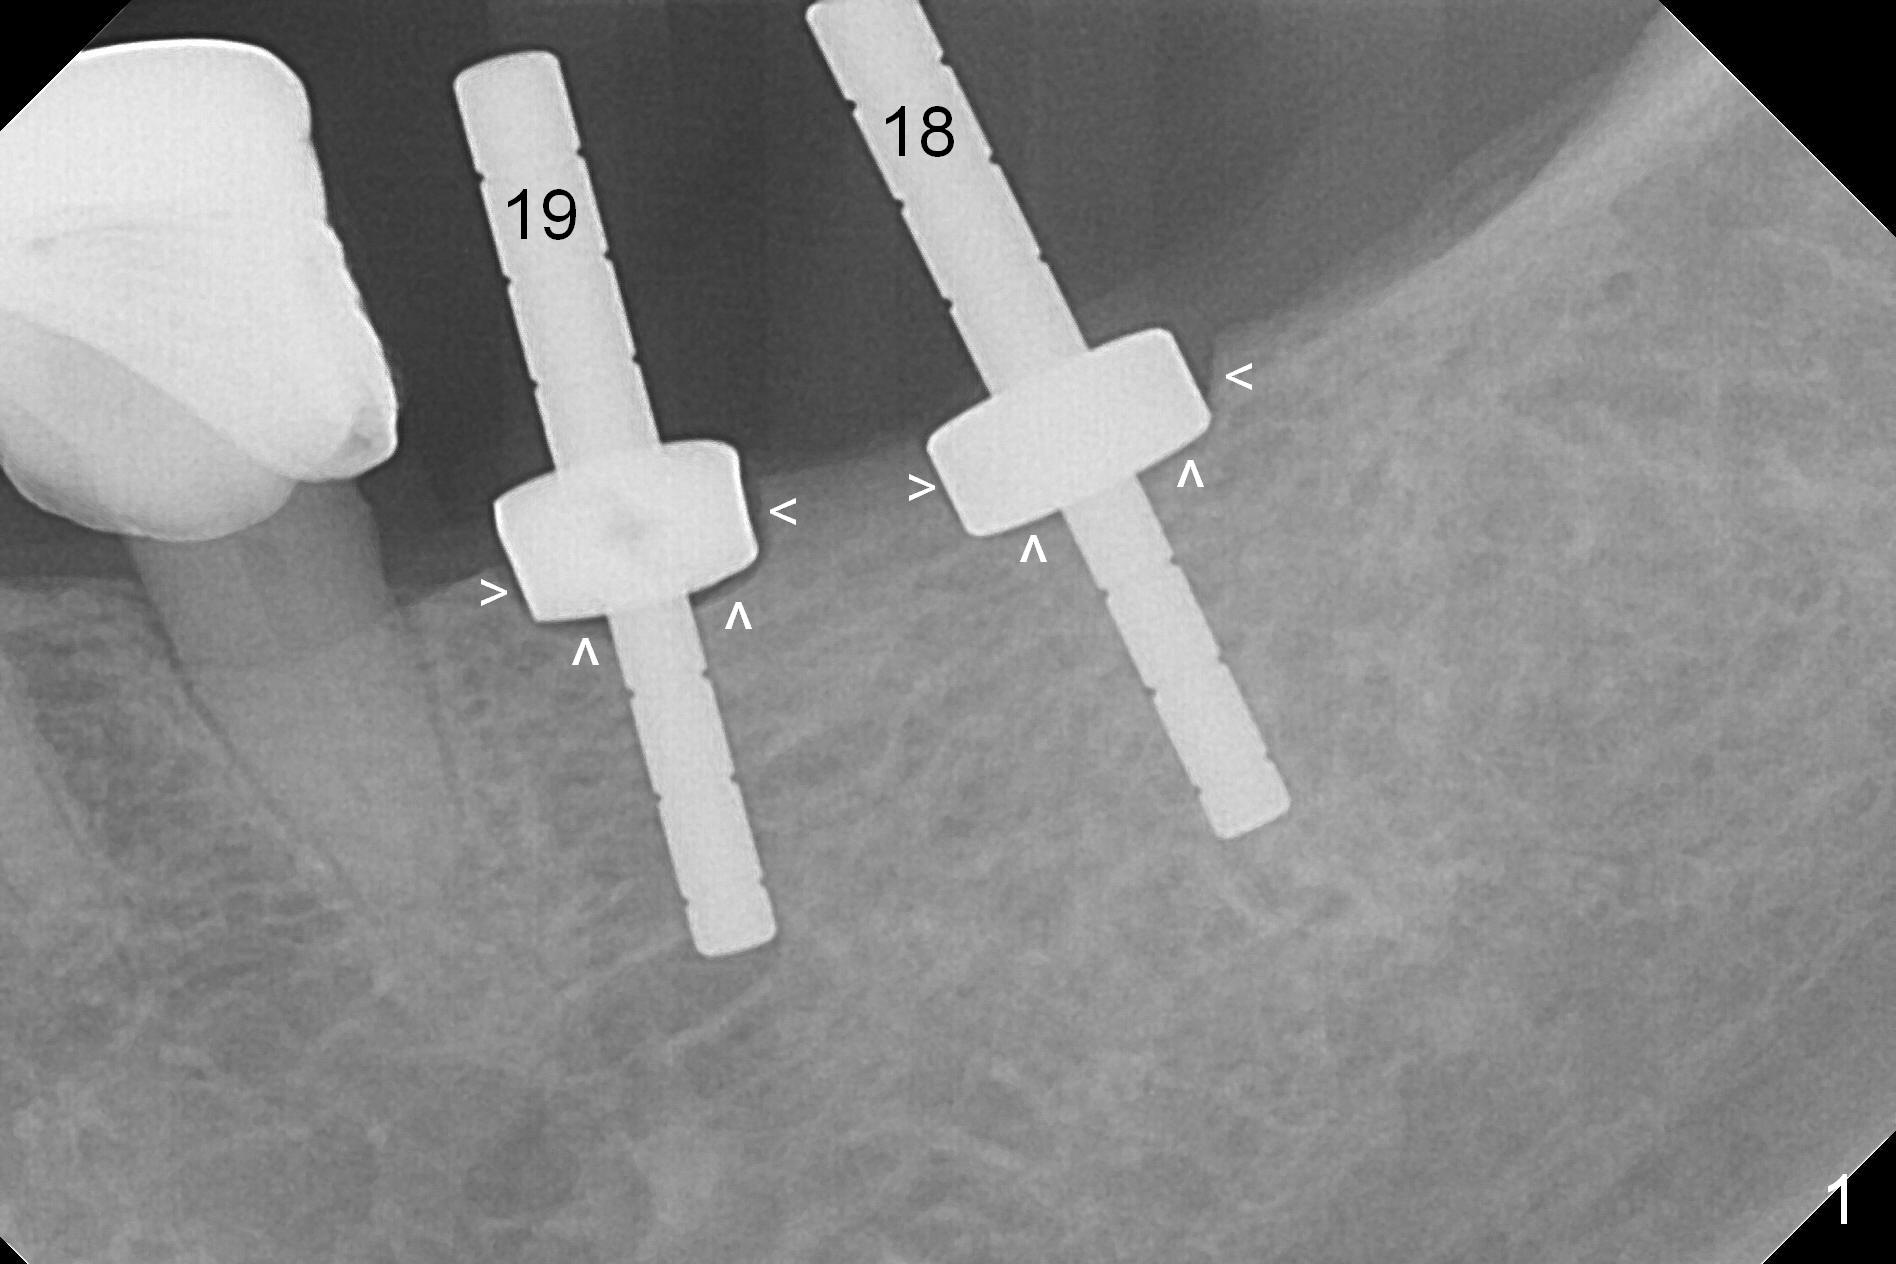

Because of the narrow ridge top at the sites of #19 and 18, it is reduced (Fig.1 arrowheads) prior to initial osteotomy with 1.6 mm pilot drill.  After Magic Drills (3.3 and 4.3 mm at #19 and 18, respectively), 4x11 and 5x9 mm IBS implants are placed with insertion torque >35 Ncm with immediate placement of pair abutments (4.5x5.7(2) and 6.5x4(2) mm, Fig.2).  In fact these sites are converted to a premolar and a 1st molar (because narrow ridge at #19).  Following GBR and suturing, periodontal dressing is applied around the abutments for increased retention.  The regional ridge reduction makes Marking Bur unnecessary (because of flat ridge top and the soft bone in this case) and more importantly there is no thread exposure upon implant placement.  The trimmed site (concavity) is favorable for bone graft and membrane placement.  One month postop, loose perio dressing is removed and replaced by a splinted nonfunctional provisional.  The implant sites look normal nearly 3 months postop; there is no bone loss (Fig.3).  Impression is taken.  The crown/abutment at #18 is loose 3 years 2 months post cementation; when the crown/abutment is retightened, the abutment remains incompletely seated (Fig.4 <) in spite of reduction of the proximal contact (arrow).  It may be due to the block of the distal crest (*).  After use of 5.5 mm profile drill, the 6.5x4(2) mm abutment remains unseated (Fig.5).  The smaller one (5x4(2) mm, Fig.6) is seated.  When the redo crown is cemented, the surrounding gingiva is healthy with a short papilla between the implant crowns (Fig.7).